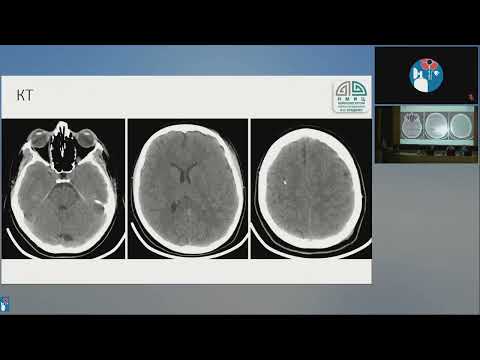

ВЧД и диаметр зрительного нерва Мурадян К.Р.

Неинвазивная и инвазивная оценка ВЧД в ОРИТ Ошоров А В